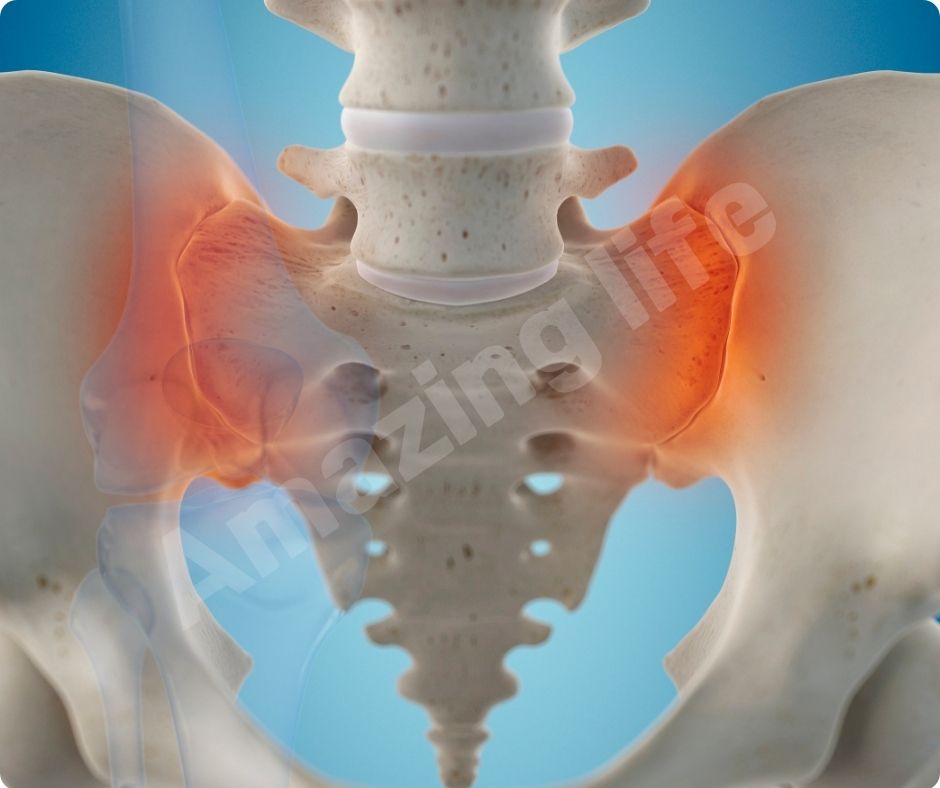

관절 통증 완화

많은 연구에서 글루코사민의 효능이 관절 통증을 완화하는 데 효과적이라는 결과가 나왔습니다. 최근 연구에 따르면, 글루코사민과 콘드로이틴 보충제를 꾸준히 섭취하면 심혈관 질환 사망률이 65%까지 감소할 수 있습니다.

염증 감소

글루코사민의 효능은 염증을 감소시키는 데도 효과적입니다. 관절염은 염증으로 인해 발생하는 경우가 많으므로, 글루코사민을 통해 염증을 줄이면 관절염 증상을 완화할 수 있습니다. 이는 자연적인 방법으로 관절 건강을 유지하는 데 유용합니다.